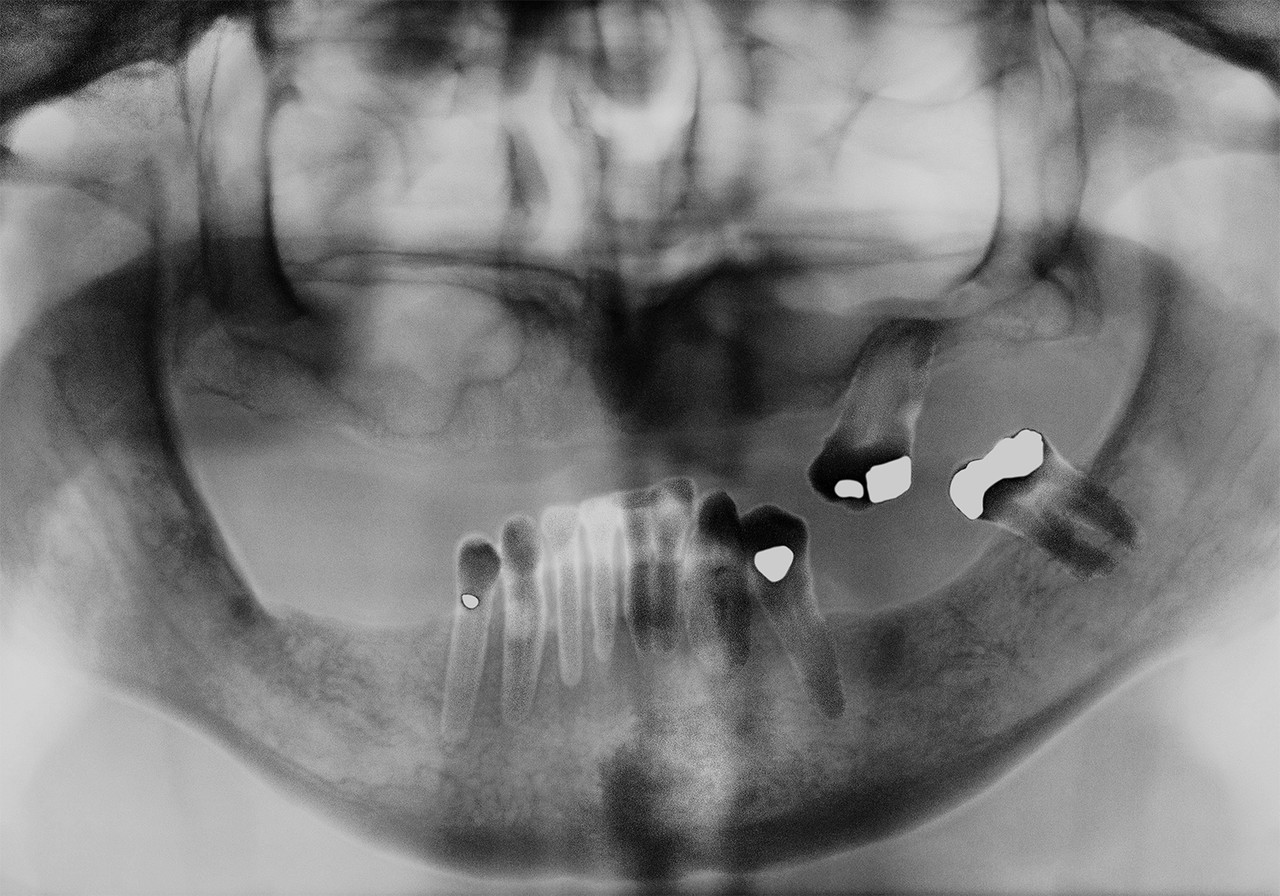

CASE 03

70대 남성, 빠른 무치악 임플란트

“치조골 상태가 양호하고 상악 전치부만 남아있어..”

첫번째 사진처럼 상악 전치부만 있는 상태로 내원하셨습니다.

사용중이던 틀니를 더 이상 원하지 않으셨고,

치조골 상태가 양호하여 바로 임플란트 계획은 세웠습니다.

상악 전치를 기준으로 임플란트 가이드를 제작하여

당일에 8개를 식립해 드렸고, 시간은 약 30분 정도 소요되었습니다.

하악은 완전 무치악 상태이셨으며, 임플란트 가이드를 제작하여

먼저 3개 식립한 후, 먼저 식립한 임플란트를 기준으로 9개를 추가로 식립해 드렸습니다.

임플란트 초기 고정이 40N 정도로 나와서 솔리드 체결하고,

상부 구조를 제작해 드렸습니다.

치료 후 약 2개월간 부드럽고 연한 음식을 드시길 권해드렸고,

이 후 정상적인 식사를 하도록 안내드렸습니다.

지금도 만족하고, 불편감 없이 사용하고 계십니다.